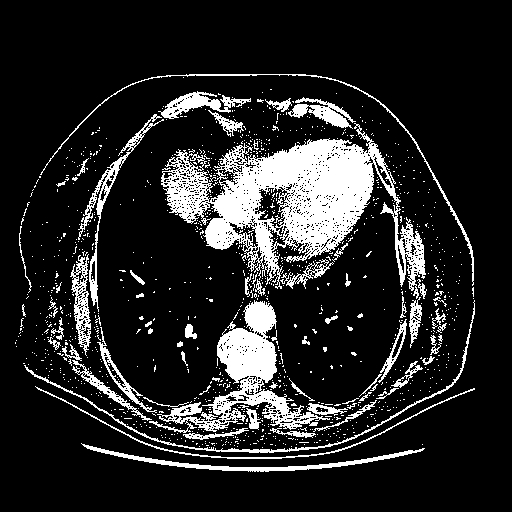

Original VENOUS CT scan

Full window (WL 1023.5, WW 4095 β†’ Low βˆ’1024, High +3071)

Actual HU range: [-1024.0, 3071.0]

Lung window (WL -600, WW 1500 β†’ Low βˆ’1350, High +150)

Actual HU range: [-1350.0, 150.0]

Mediastinum window (WL 40, WW 400 β†’ Low βˆ’160, High +240)

Actual HU range: [-160.0, 240.0]